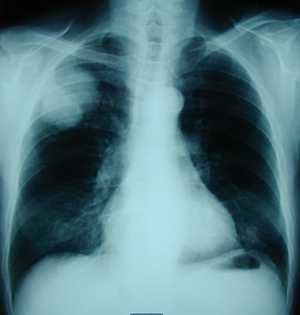

Εικόνα 1

Οπισθιοπρόσθια ακτινογραφία θώρακος που δείχνει όγκο στο δεξιό άνω λοβό.